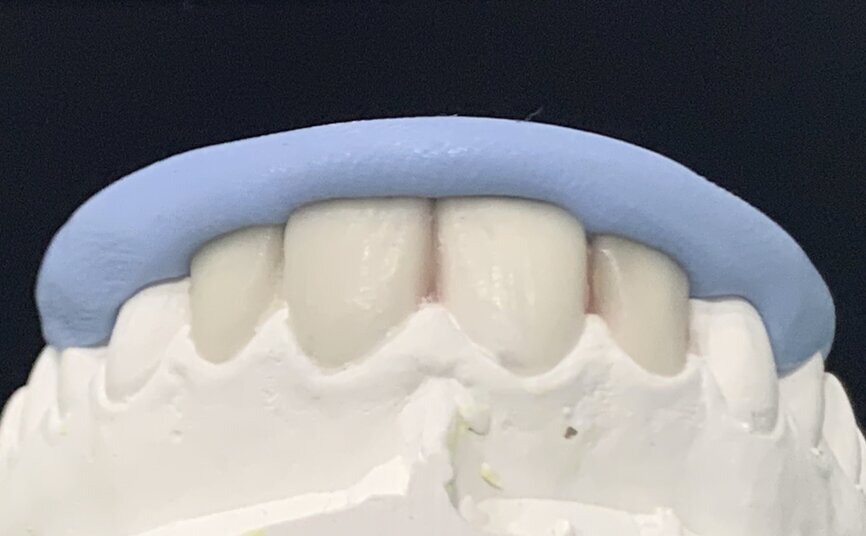

After the treatment planning discussion, the patient requested to proceed with direct resin-bonded composite veneers to enhance her smile. After the old composite fillings were removed (Fig 3, 4), smile design, was done to restore the golden proportion by modifying the shape and size of the teeth. Based on the smile design a mock-up was created to help obtain patient approval on the expected outcome and fabricate the silicone index.

Fig 7 : Direct mock-up to assess occlusion and obtain patient approval

Direct mock-up

Silicon mold was used to create a direct mock-up trial to ensure proportion compatibility, occlusion and obtain patient approval.

Tip: checking the occlusion at this stage helps identify the points of interference that might affect the final restoration design and minimize adjustments.